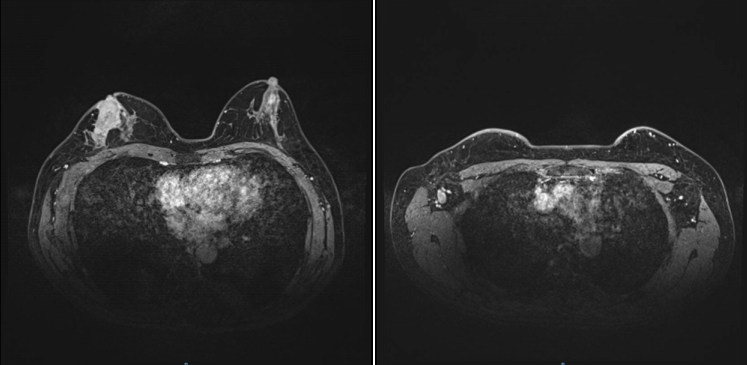

2022-4-19,乳腺MR:右乳外上象限腺体内(约9-12点钟方向,前中带区)条片影,大小约2.5×0.7cm,较前明显缩小、强化减低。右侧腋窝数个小淋巴结,较大者短径约0.5cm,较前缩小。

图5.乳腺MR(2022-4-19)

2022年04月20日在全麻下行“右乳癌改良根治术+胸壁缺损修复术”,术后病理:新辅助治疗反应评估(Miller-payne分级系统):5级:切片上肿瘤部位未见恶性肿瘤。病理学分期:ypTisN0Mx;淋巴结转移情况总计(阳性淋巴结/淋巴结总数):0/15;

治疗后评价:(右乳癌新辅助治疗后肿物)病理完全缓解。